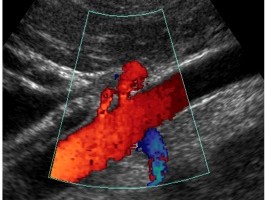

Con l’ecografia, associata alla tecnica doppler , si può esaminare il flusso del sangue nel cuore e nei vasi.

Un fascio d’ultrasuoni che colpisce un liquido che scorre in un vaso può far capire la direzione e la velocità del flusso.

Mettendo insieme l’ecografia ed il doppler è possibile osservare non solo le eventuali modificazioni della forma del cuore, delle arterie e delle vene, ma anche le caratteristiche del flusso del sangue al loro interno.